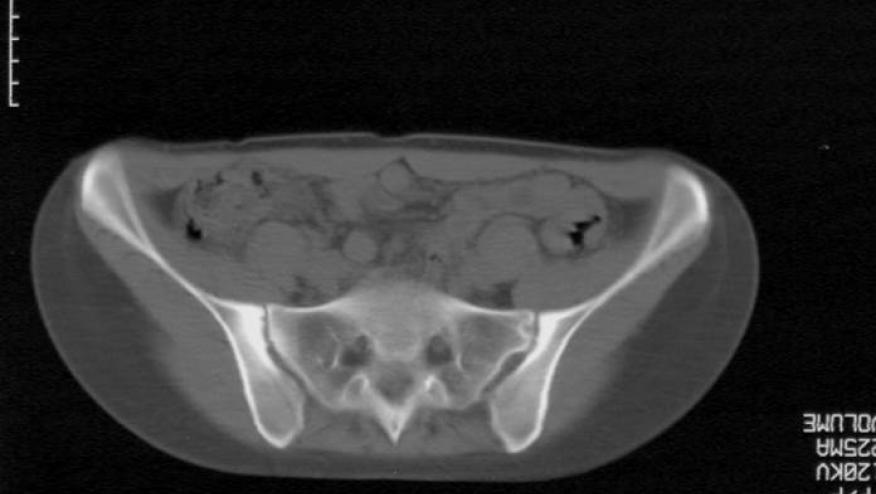

The FDA has approved the IL-17A inhibitor Taltz (ixekizumab) for the treatment of adults with active ankylosing spondylitis (AS: also known as radiographic axial spondyloarthritis).

Approval is based on the COAST trials in AS. The COAST-V trial studied IXE in biologic naive AS/SpA patients and the COAST-W trial involved patients previously to TNF inhibitors.